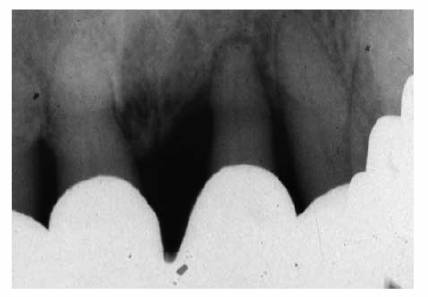

system as the root canal obturation material (Figures 19-53A

and B). In a

recent study, Ray and Trope evaluated the radiologic quality of both coronal

and canal obturations.24 It was demonstrated that a tooth with good

coronal and root seals had the best rate of absence of periapical lesions

(91.4%). Good restoration resulted in significantly less incidence of

periapical lesions than good endodontic filling (80% versus 75.7%). Poor

restoration resulted in significantly more periapical lesions than poor

endodontic fillings (48.6% versus 30.2%).